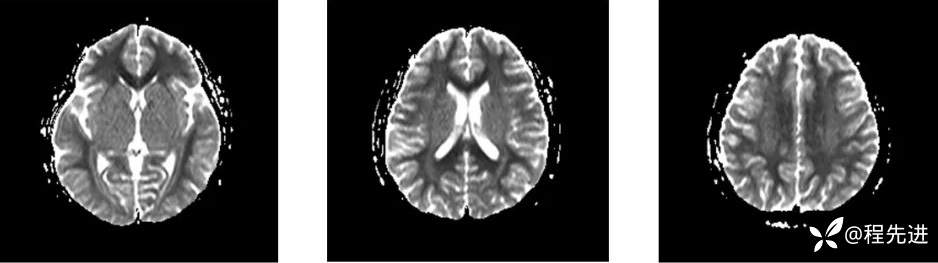

MRI: